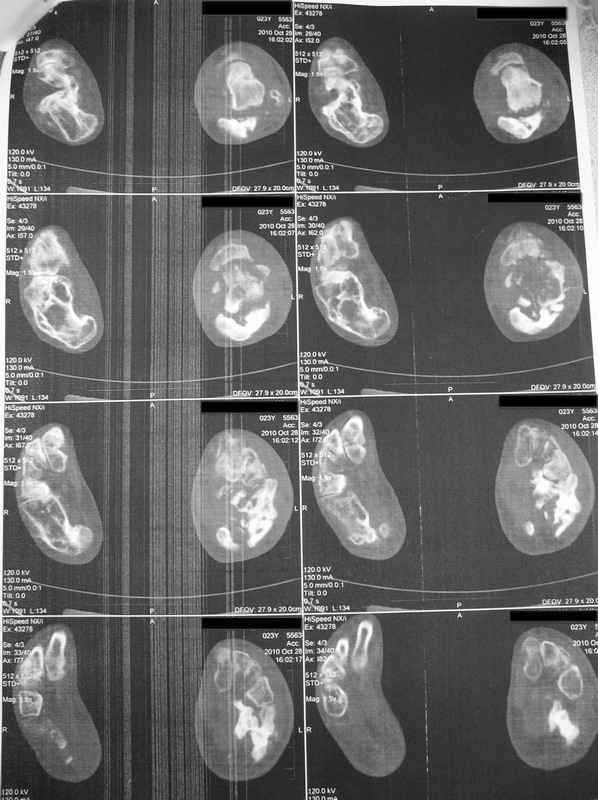

Молодая девушка со сросшимися многооскольчатыми переломами пяток и голеней.Young girl with fractures of the calcaneus Больная Н., 25 лет, падение с высоты (2008 г.). Жалобы на боли в области голеностопных суставах, в области пяток при ходьбе. Лечилась в аппаратах внешней фиксации по поводу открытых оскольчатых переломов обеих голеней, переломов пяток. Далее по поводу несросшихся переломов голеней –ЧКОС аппаратами внешней фиксации. Переломы срослись, аппараты демонтированы весной 2010г. В левой пяточной области в месте проведения спицы имеется сукровичное отделяемое. При ревизии гноя нет. Чем помочь девушке?

Patient N., age 25, falls from heights (2008). Complaints of pain in the ankles, in the heel when walking. She was treated by external fixation on open comminuted fractures of both legs, fractures of the calcaneus. Then she was treated by external fixation from nonunion of both legs. Now fractures are fused, apparatuses removed in the spring of 2010. How to help a girl?